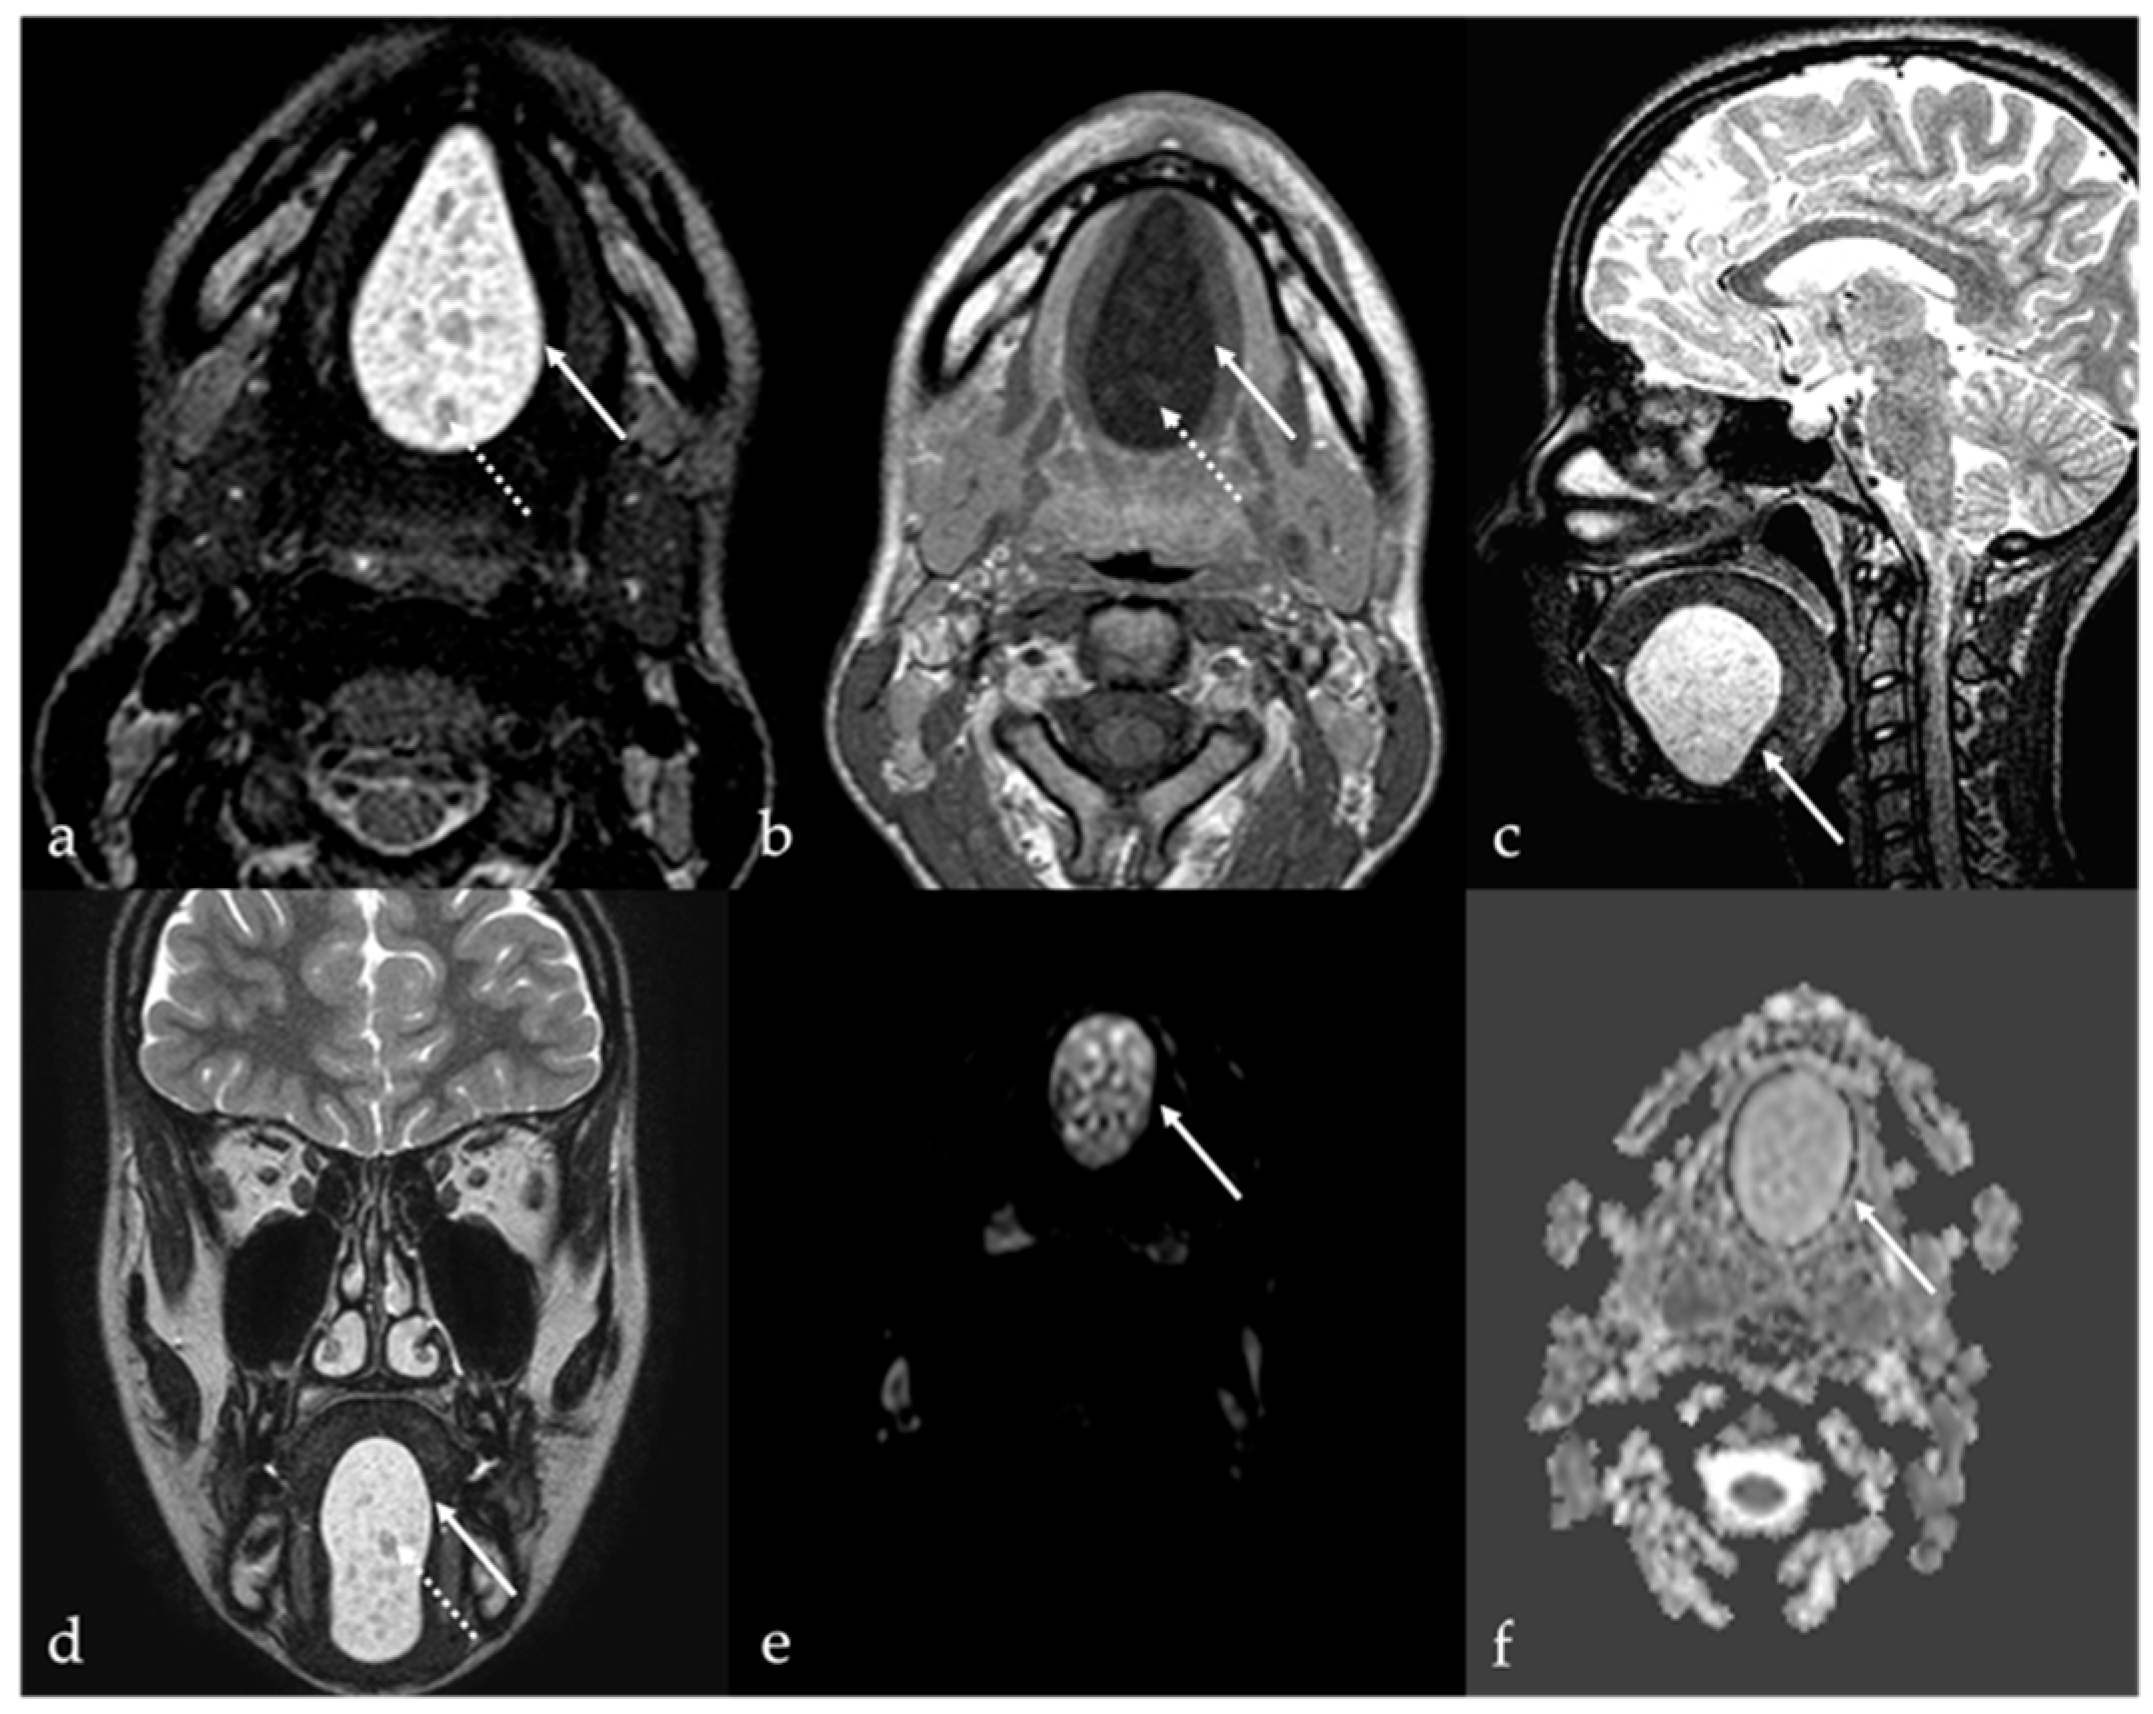

7.1. Thyroglossal Duct Cyst

7.2. Ectopic Thyroid Tissue

| Thyroglossal duct cyst [15] Ectopic thyroid tissue [16] | Cyst Same features as thyroid tissue | Lingual tonsil mucous retention cyst Squamous cell carcinoma and lymphoma of the tongue base |